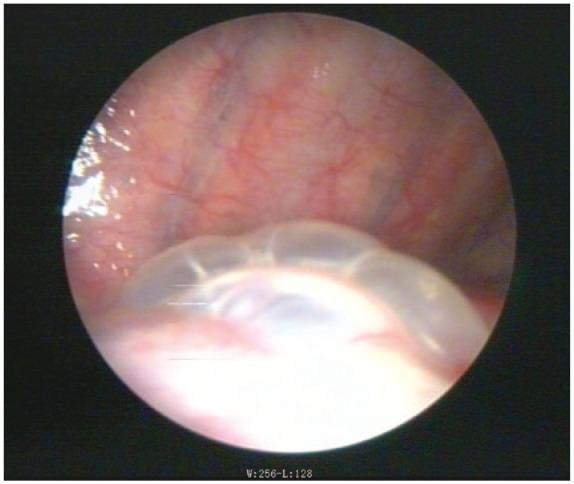

Three male patients with spontaneous pneumothorax were treated; medical thoracoscopy-assisted argon plasma coagulation combined with autologous blood pleurodesis was conducted for all patients whose duration of the air leak exceeded 7 days. We systematically reviewed all of the relevant literature to analyze and sum up the treatments of secondary spontaneous pneumothorax.

The air leaks were all sealed and no recurrence of pneumothorax was reported. No complications of fever, bleeding, or signs of infection were observed during the process.

The authors believe that the combination of medical thoracoscopy-assisted argon plasma coagulation and autologous blood pleurodesis is safe and effective. However, due to the number of patients included in this uncontrolled case study, more cases will be collected in the future.